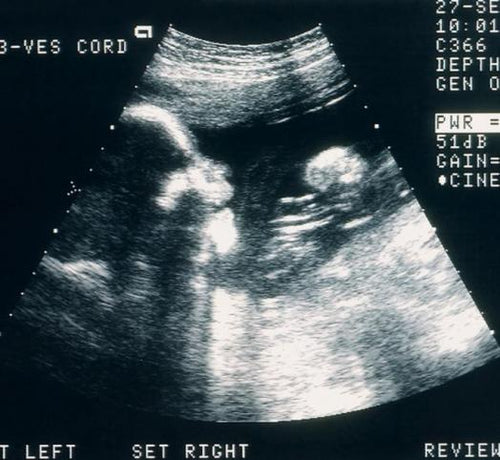

Enceinte, on a un peu tendance à remettre à plus tard le rendez-vous chez le dentiste... A tort. L’hygiène et la santé bucco-dentaire peuvent en effet avoir un impact sur la grossesse et vice-versa.